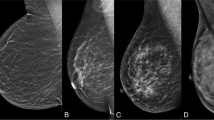

AB-MRI was performed using a 1.5T or 3.0T MRI system (Signa HDxt or Discovery 750; General Electric Medical Systems, Milwaukee, WI, USA). All patients were imaged in the prone position using a dedicated eight-channel bilateral breast coil (General Electric Medical Systems). Following the acquisition of transverse localizer images, sagittal fat-suppressed T2-weighted fast spin-echo images were acquired with a minimum repetition time and echo time (1.5T, 4000–4200/100 ms; 3.0T, 3400–3600/100 ms), a 20-cm field of view, 4-mm sections with no gap, and a 256 × 224 matrix. Before and immediately after contrast injection, three-dimensional sagittal T1-weighted fat-suppressed fast spoiled gradient-echo sequences with parallel imaging were acquired with a minimum repetition time and echo time (1.5T, 6.9/3.4 ms; 3.0T, 6.3/2.4 ms), a 10° flip angle, an 18-cm field of view, 1-mm sections with no gap, and a 288 × 150 matrix at 1.5T or a 288 × 192 matrix at 3.0T MRI system (Fig. 1). The total acquisition time was only 8.5 min. Gadoterate meglumine (Dotarem; Guerbet, Aulnay-Sous-Bois, France) was injected into the antecubital vein at a dose of 0.1 mmol/kg body weight and a rate of 3 ml/s using an automated injector (Spectris Solaris, Medrad Europe, Maastricht, The Netherlands), followed by a 20-ml saline flush. The precontrast T1 images were subtracted from the corresponding postcontrast images to achieve subtraction images. Subtraction was automatically achieved on a pixel-by-pixel basis using the software subtraction function available on the console. Reformatted images with a maximum-intensity projection (MIP) in the craniocaudal and mediolateral directions were created from the subtraction images.

The reader initially reviewed the subtracted images to determine the presence or absence of significant enhancement. If there was significant enhancement, its enhancement and morphology were assessed on the subtraction images and fat-suppressed T2-weighted images (Fig. 2). MIP images were used to estimate the lesion size and distance from the nipple and assess the distribution of nonmass enhancements.

Order of interpretation of abbreviated breast MRI (AB-MRI) sequences acquired for the screening of women with a history of breast cancer surgery. Subtracted T1-weighted images are viewed first (a), followed by fat-suppressed T2-weighted images (b) and subtracted maximum-intensity projection (MIP) images (c)